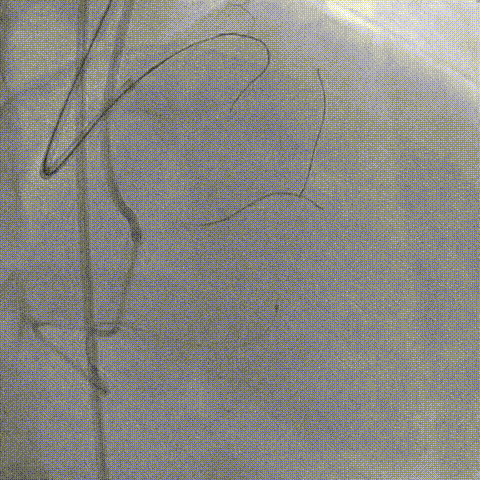

LAD Stent Synergy 3.5*38mm

Ballon QM 4.0*12mm, 5.0*8mm Dilatation & POT

LAD post-IVUS check RUN 3

Final result: TIMI flow grade 3